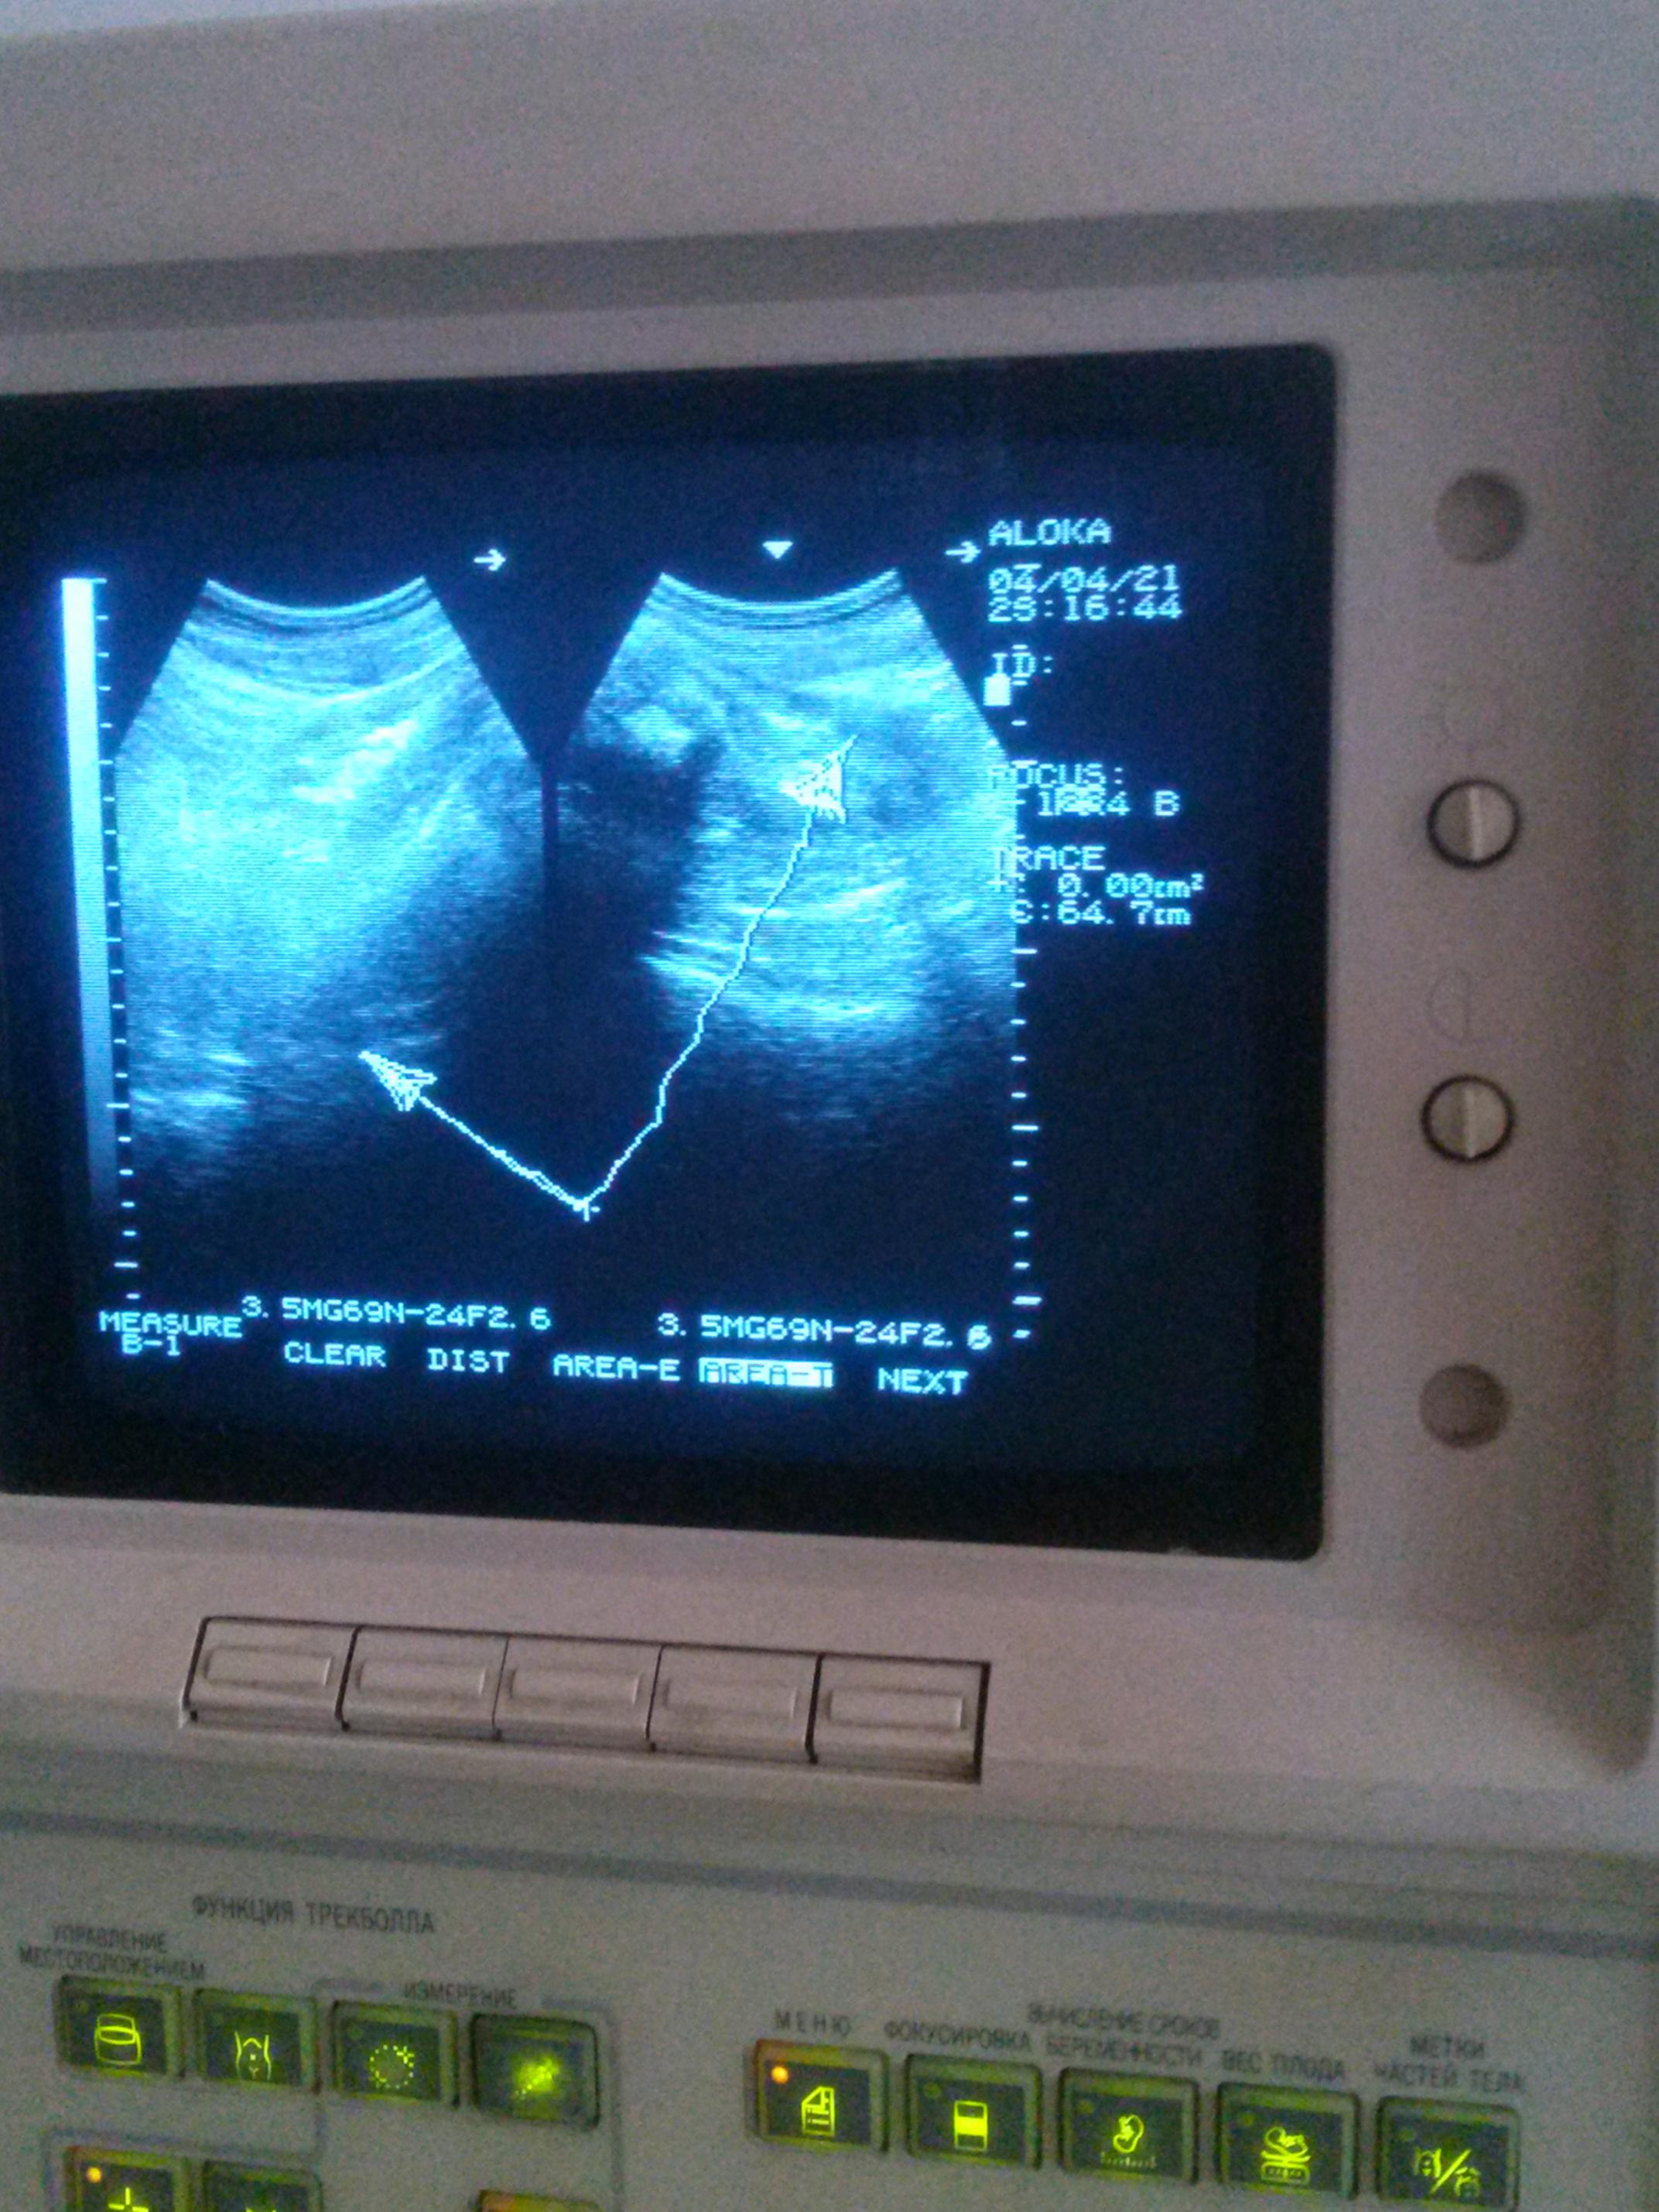

Да.., ходили на УЗИ - вначале жена - отличное состояние печени - и это после жирового гепатоза! У меня скромнее, но особых беспокойств нет. Есть много остаточных явлений.., в том числе в легких, возможно после простудных, или даже химий, да и по возрасту всего по немногу...